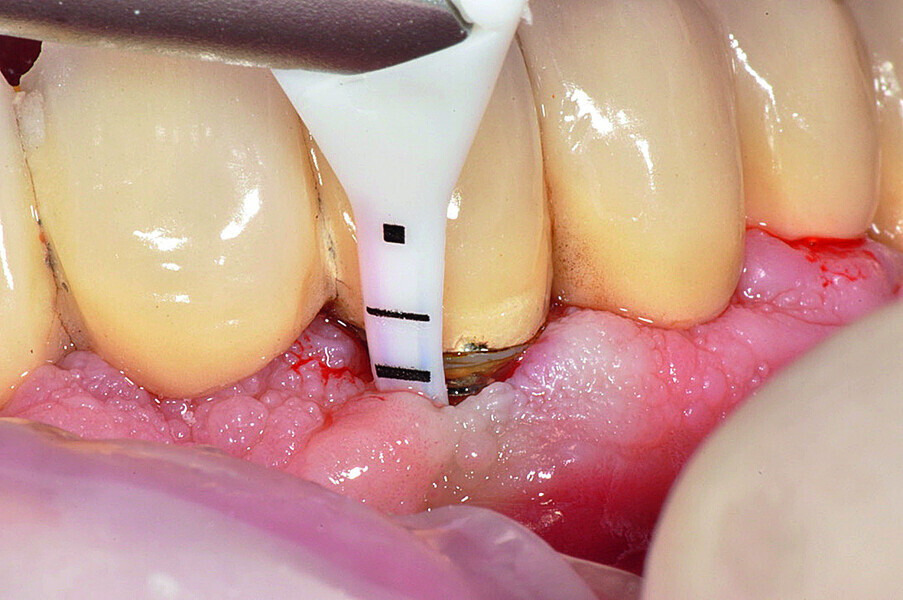

Fig. 1b: Implant in position #14 affected by peri-implantitis: periimplant probing a) with the prosthetic crown in situ and b) after prosthetic crown removal.